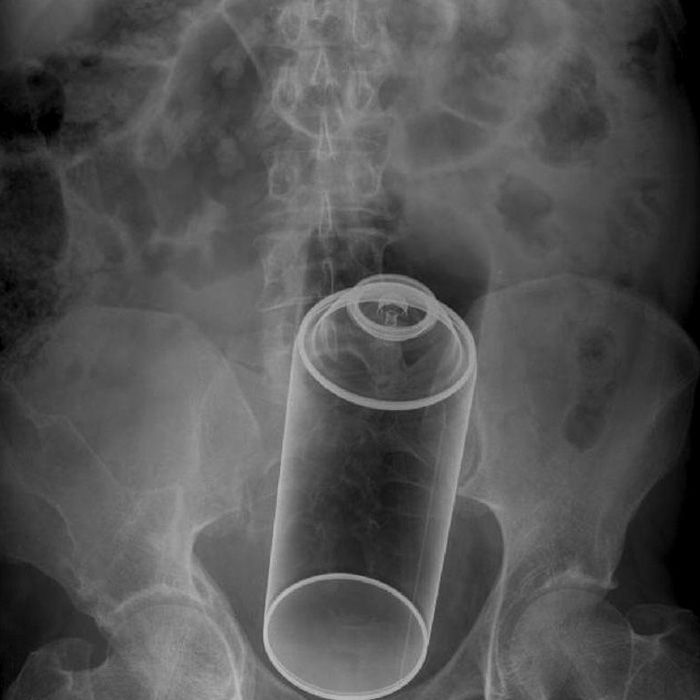

Dr Frank Gaillard

Yes, anal toys are great when they are long and cylindrical, but not when it’s a bottle of bug spray!